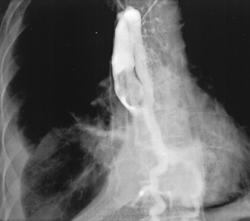

Ангиосаркома

Приложения:

14.mik_.slayd47.jpg

Ангиосаркома - наиболее частая разновидность, составляющая 33% первичных злокачественных опухолей. У мужчин встречается в 2- 3 раза чаще, чем у женщин. Опухоль может поражать любые отделы сердца, наиболее часто - правое предсердие.

Ангиосаркома макроскопически представляет собой плотное бугристое образование, инфильтрирующее ткани. На разрезе видны очаги некроза и кровооизлияний. Микроскопически определяются веретенообразные, полигональные или округлые клетки, образующие синцитий и складывающиеся в беспорядочно расположенные тяжи. Характерным является образование различных по размерам и форме сосудистых полостей, заполненных кровью и сообщающихся между собой. Между клетками опухоли находятся рыхлые сети аргирофильных волокон, напоминающих базальную мембрану.